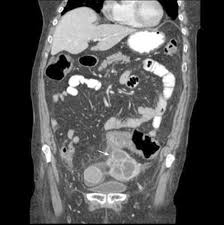

Frontiers Hernia And Cancer The Points Where The Roads Intersect Surgery from www.frontiersin.org The differential diagnosis of diverticulitis vs. I am 41 and went my whole life without a uti, but lat year got one that was treated, but after treatment, i still had symptoms and blood present in urine. Hi, please can anyone help me, am in so much pain. Ovarian cancer starts in the cells lining the ovaries. 10% of women can also have ovarian cancer. dr. It's important to know what the warning signs are, as well as when to seek medical attention. Misdiagnosis of bowel conditions can take on a few different forms, but the most obvious is that you were diagnosed with a condition you do not have. This article will give you a starting point to gather the information you need.

Differential Diagnosis For Female Pelvic Masses Intechopen from www.intechopen.com If my doctor had been listening to me, i would have been diagnosed at stage i instead of almost a iii more than one year later! I am 41 and went my whole life without a uti, but lat year got one that was treated, but after treatment, i still had symptoms and blood present in urine. Chait's practice interests include digestive conditions such as colon cancer, gastrointestinal endoscopy and internal medicine. The differential diagnosis of diverticulitis vs. Hi, please can anyone help me, am in so much pain. Women presenting with symptoms of ovarian cancer often receive a diagnosis of ibs, diverticulitis, urinary tract infection or changing menopausal status. 10% of women can also have ovarian cancer. dr. Spotting can be linked to several different health issues, and one of them is ovarian cancer.

This study aimed to evaluate the risk of colon diverticulitis ovarian cancer. The differential diagnosis of diverticulitis vs. However, just as the conditions have similarities, they have many differences. Could your irritable bowel syndrome (ibs) really be ovarian cancer? When a woman is diagnosed with diverticulitis the doctor should also screen for ovarian cancer.